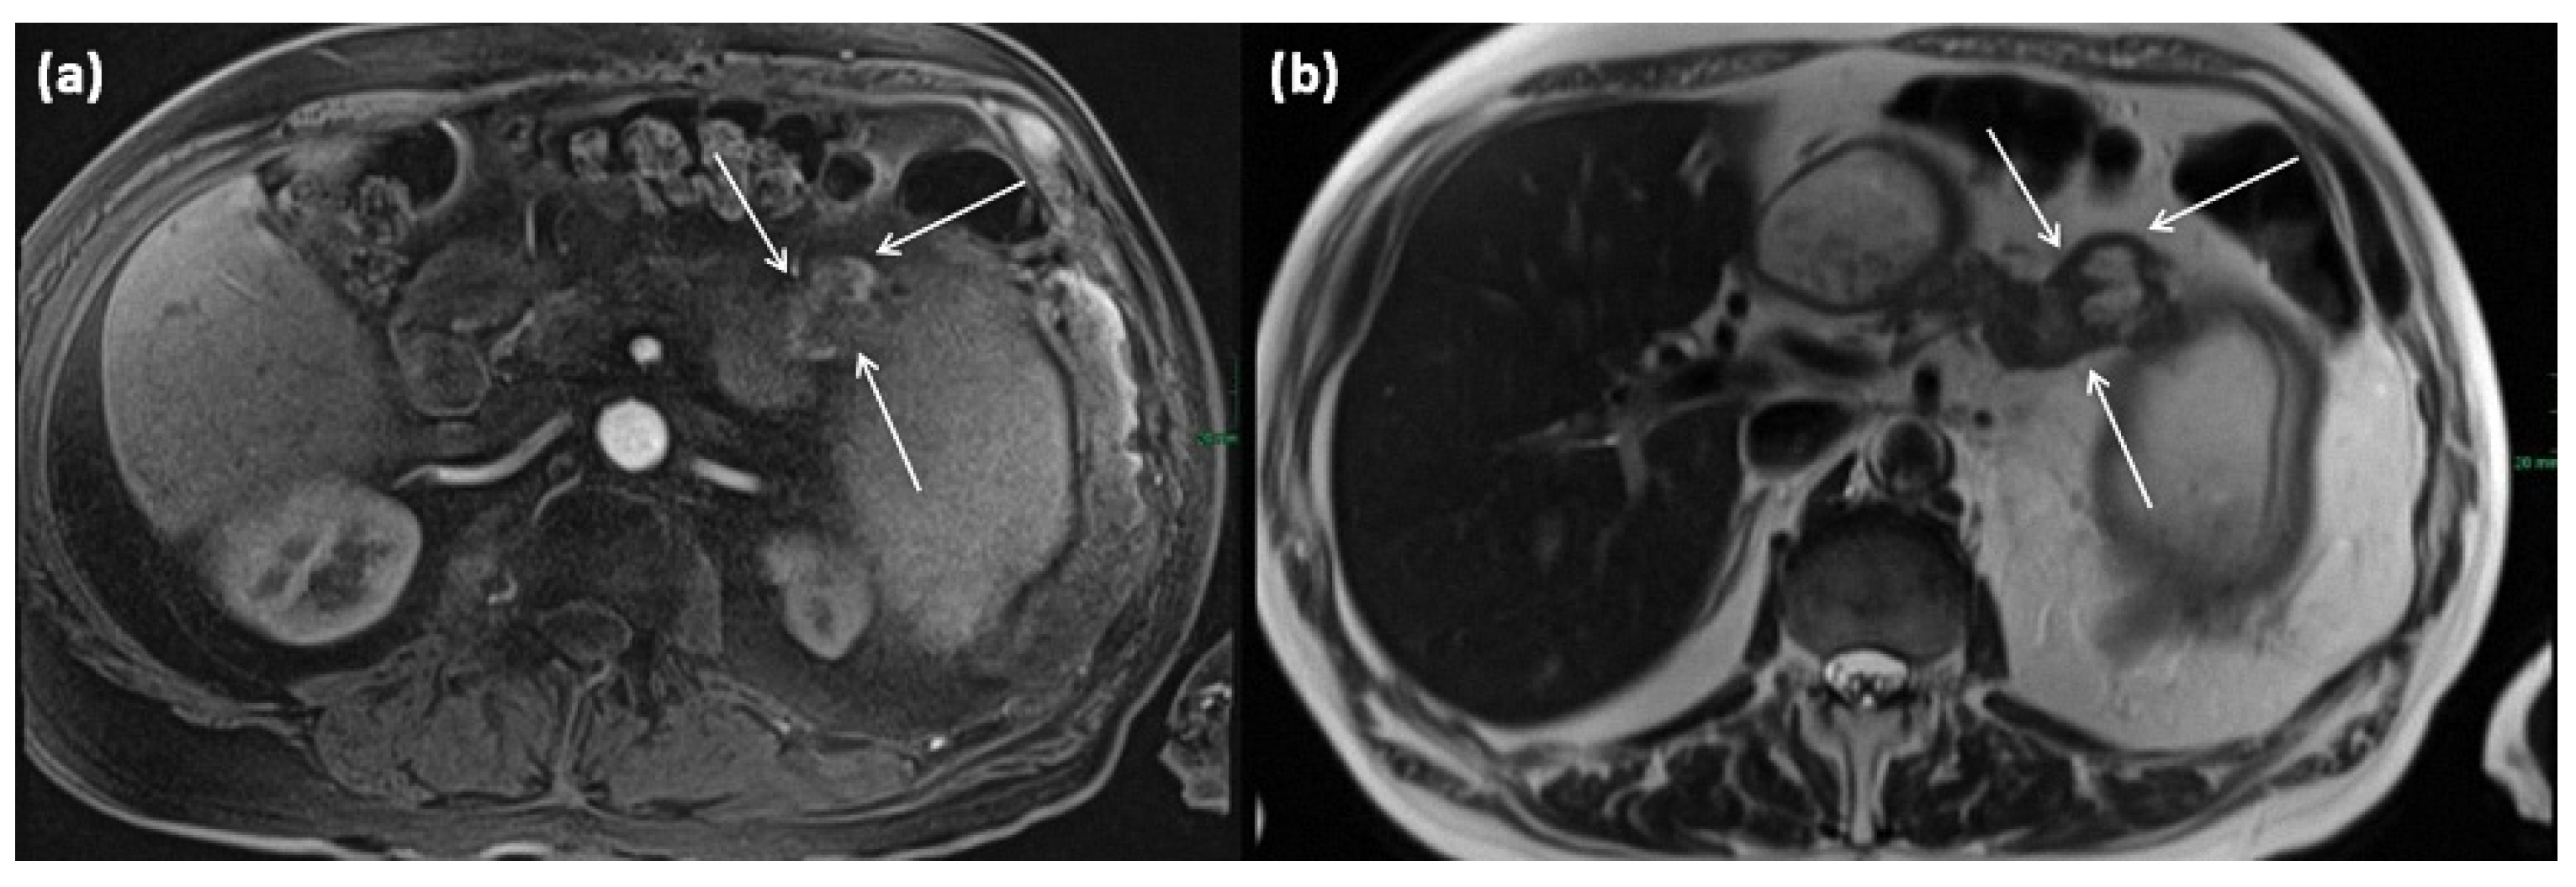

In addition to the two most common types, the mixed type is delineated as a third entity; this has ductal extensions of both main and branch ducts (Figure 15). In spite of that, the mixed type has the same risk of malignant transformation as the main duct type, so surgery is recommended (grade 2C recommendation) [].

Figure 15.

MRI of a 39-year-old female patient with T2w (a) and magnetic resonance cholangiopancreaticography (MRCP) (b). Images show a clear demarcated main duct dilatation in terms of a main duct IPMN (double arrow). Furthermore, the extension of a branch duct (arrow) can be seen, thus of a combined main and branch duct IPMN is present (mixed-type).

Figure 16.

MRI of a 60-year-old patient with a partly cystic and partly solid mass of the pancreatic tail. Arterial T1w after gadolinium-based contrast administration (a) typical peripheral hyperarterilization (arrows) can be seen. In T2w, solid as well as cystic parts are present (b).